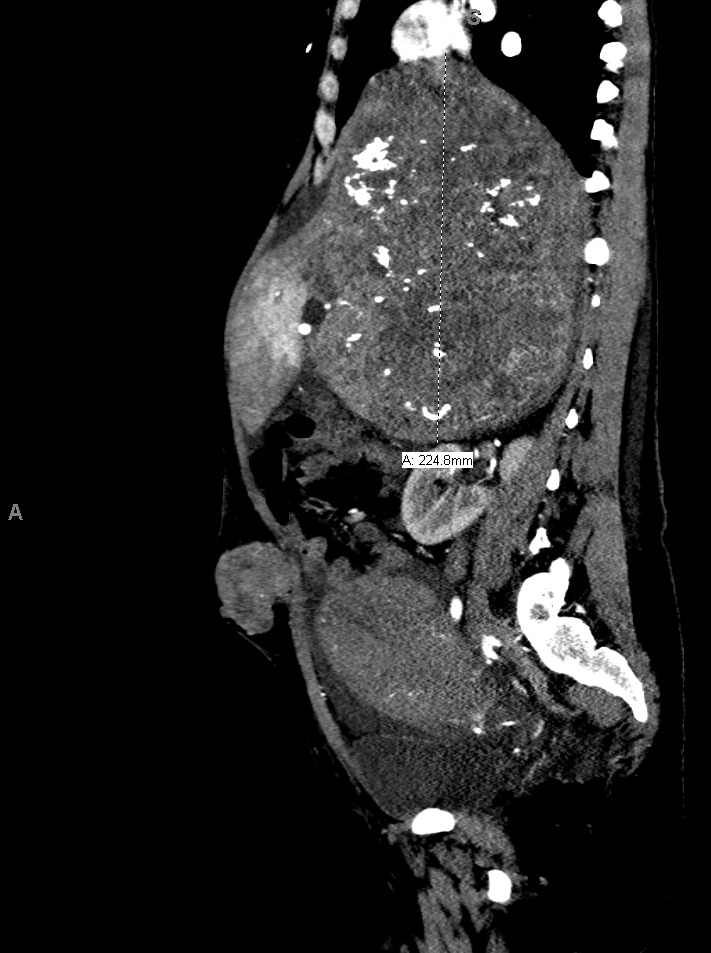

The patient delivered by spontaneous vaginal delivery at 37 weeks gestation. Her tachycardia persisted postpartum with heart rates exceeding 140 beats per minute, still of unexplained etiology. She developed a leukocytosis within the normal postpartum range but remained afebrile and without fundal tenderness. Due to increasing suspicion for malignancy, a computed tomography (CT) scan of the abdomen and pelvis was obtained, which showed a 19.0 x 17.7 x 22.5 cm heterogeneously enhancing soft tissue retroperitoneal mass with internal calcifications (Figures 1 and 2) and heterogeneously enhancing masses of various sizes in the liver and abdominal wall concerning for metastatic GIST (Figure 3). On postpartum day six, CT angiography of the chest was performed due to persistent tachycardia in the setting of a new diagnosis of a malignancy, which showed a right anterior lower lobe segmental and subsegmental pulmonary embolus. The patient was started on therapeutic low-molecular-weight heparin and trans-thoracic echocardiography was performed, which was unremarkable.